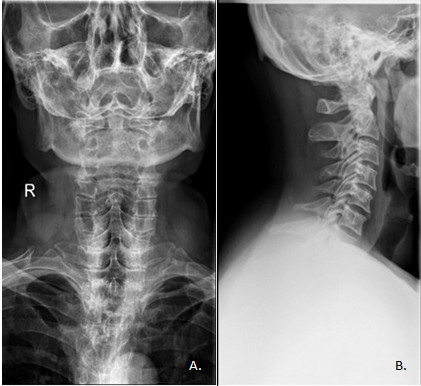

Badania obrazowe kręgosłupa i stawów

No i dochodzimy do tematu, który jest mi szczególnie bliski jako fizjoterapeucie i osteopacie. Kręgosłup i stawy – to właśnie one najczęściej bolą moich pacjentów.

Diagnostyka zmian zwyrodnieniowych

Choroba zwyrodnieniowa stawów to nie choroba, to proces naturalny – jak rdza na metalu. Z wiekiem chrząstka stawowa się zużywa, szpara stawowa zwęża, pojawiają się osteofity (kostne wyrośla). To normalne, tylko czasem daje objawy – ból, sztywność, ograniczenie ruchomości.

Zdjęcie rentgenowskie pokazuje stopień zaawansowania zmian zwyrodnieniowych. To podstawa diagnostyki w ortopedii i reumatologii. Na podstawie RTG lekarz może ocenić, czy wystarczy leczenie zachowawcze (fizjoterapia, leki przeciwbólowe), czy trzeba myśleć o operacji – np. wszczepieniu endoprotezy stawu.

Wykrywanie dyskopatii i urazów kręgosłupa

Dyskopatia – czyli uszkodzenie krążka międzykręgowego – to częsty problem, szczególnie w odcinku lędźwiowym. Krążek wyrywa się poza obrys kręgów, uciska korzeń nerwowy, a Ty masz strzelające bóle do nogi, mrowienie, osłabienie mięśni.

Rezonans magnetyczny kręgosłupa to tutaj król diagnostyki. Pokaże Ci dokładnie, który krążek jest uszkodzony, jak duża jest przepuklina, czy uciska rdzeń czy korzeń nerwowy. Na podstawie MRI neurochirurg decyduje, czy trzeba operować, czy wystarczy rehabilitacja.

Tomografia komputerowa jest niezbędna przy złamaniach kręgów – szczególnie po urazach wysokoenergetycznych, wypadkach, upadkach z wysokości. Pokazuje dokładnie przebieg linii złamania, stopień przemieszczenia odłamów, czy jest uszkodzony rdzeń kręgowy.